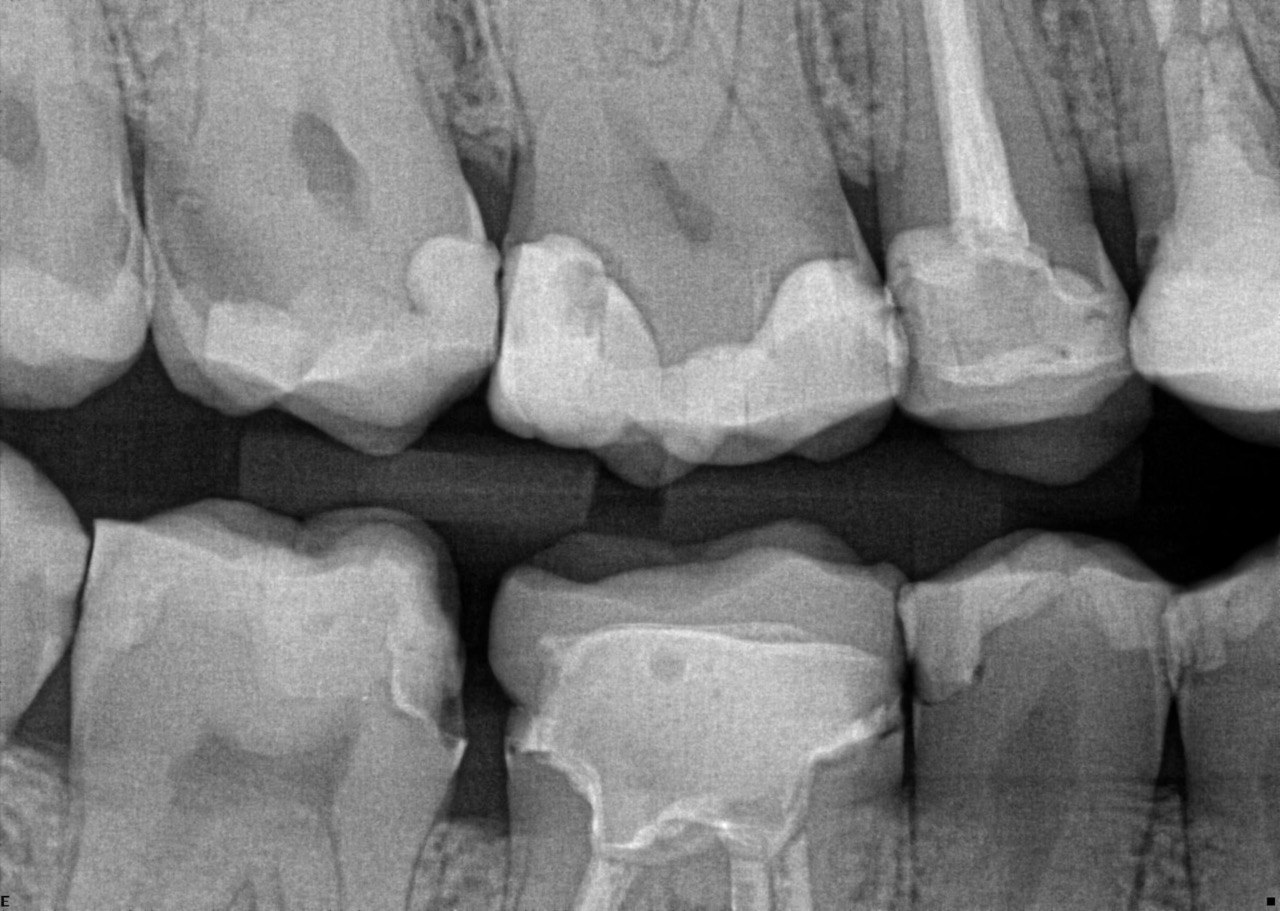

Question 30: What option can be seen on the lower jaw of the following X ray?

Question 31: Which options can be selected for the following X ray?

Question 32: Which surface need restoration?

Question 33: What is the condition in mesial of tooth # 4.6?

Question 34: What is the level of caries on mesial of the tooth # 1.6?

Question 35: Which surface shows recurrent caries?

Question 36: What is the caries on distal surface tooth # 1.5?